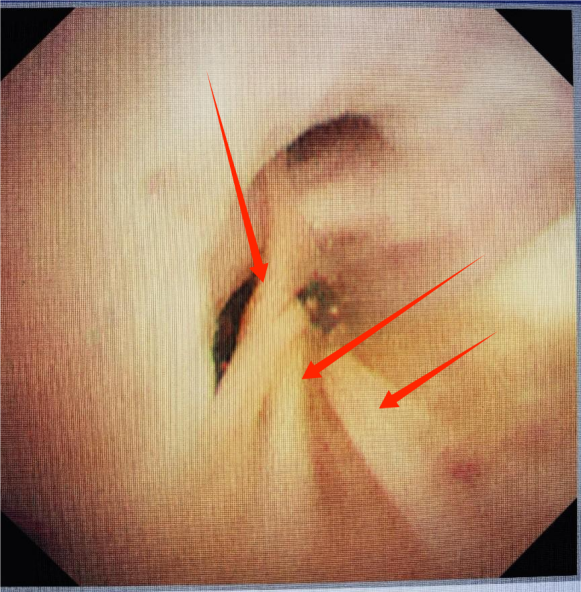

发现支气管软化,指导针对性制定呼吸康复计划及随访。

支气管软化